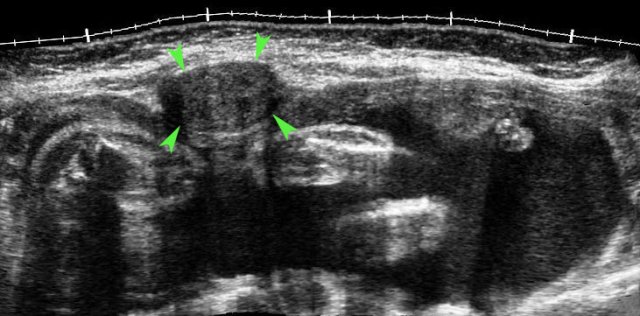

case 3

This patient was submitted for suspected perforated appendicitis.

US showed free fluid and to the right of the uterus (U.), a gestational sac containing a living fetus.

Fetal heartbeat was documented by TVUS with M-mode (right lower image).

A living fetus is found in less than 10 % of all ectopic pregnancies.